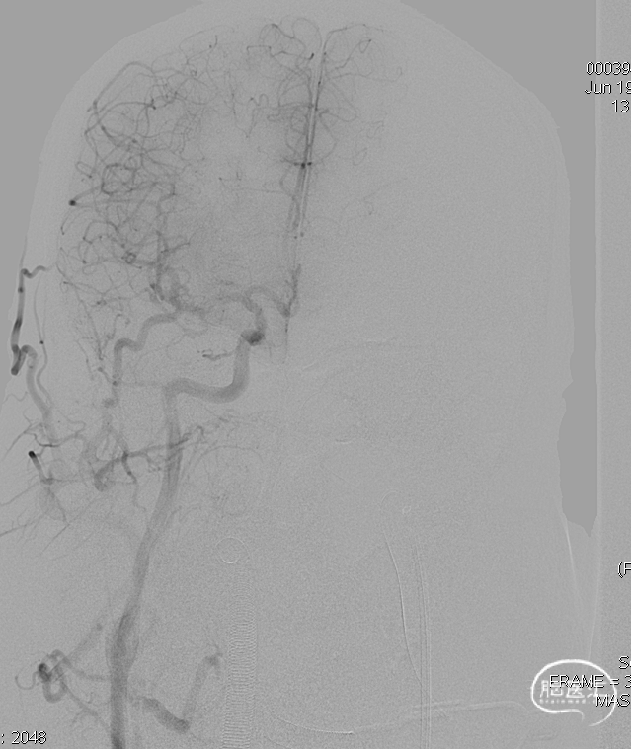

术后右侧颈总造影,未见向瘘口供血。

术后铸胶形态及CT下铸胶位置,可见瘘口位于左侧舌下神经管区域。